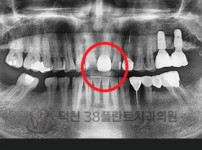

치료전후